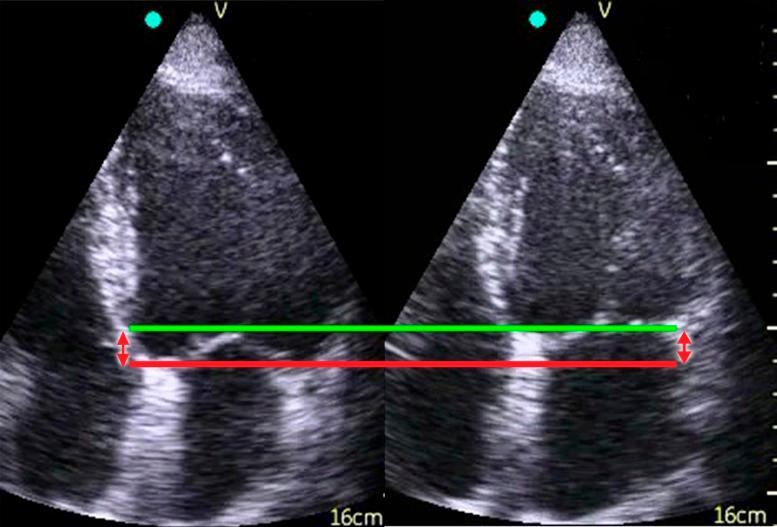

Feasibility study in general practice, seven GPs in three different Norwegian primary care centres participated. Ninety-two patients with reduced or at risk of developing reduced LV function were examined by their own GP using pUS. The scan (<5 minute) was done as part of a routine appointment. A cardiologist examined the patients <30 minutes afterwards with both a laptop scanner and pUS. Measurements of the septal mitral annular excursion (sMAE) were compared.

In 87% of the patients, the GPs were able to obtain a standard view and measure the sMAE. There was a non-significant mean difference in sMAE between GP pUS and cardiologist laptop scanner of -0.15 mm 95% confidence interval (-0.60 to 0.30) mm. A comparison of the pUS recordings and measurements of sMAE made by GP versus cardiologist revealed a non-significant mean difference with acceptable 95% limits of agreement (-0.26 ± 3.02 mm).

在全科医学中的可行性研究,来自三个不同的挪威初级保健中心的 7 名全科医生参与了该研究。92 名 LV 功能降低或有降低风险的患者由其自身 GP 使用 pUS 进行检查。扫描(<5 分钟)作为常规预约的一部分进行。<30 分钟后,心脏病专家使用笔记本电脑扫描仪和 pUS 对患者进行检查。比较了间隔二尖瓣环运动(sMAE)的测量结果。

在 87%的患者中,GP 能够获得标准视图并测量 sMAE。GP 的 pUS 和心脏病专家的笔记本电脑扫描仪之间的 sMAE 平均差异无统计学意义(-0.15mm,95%置信区间(CI)为-0.60 至 0.30)mm。GP 与心脏病专家对 pUS 记录和 sMAE 测量值的比较显示,平均差异无统计学意义,具有可接受的 95%一致性界限(-0.26±3.02mm)。